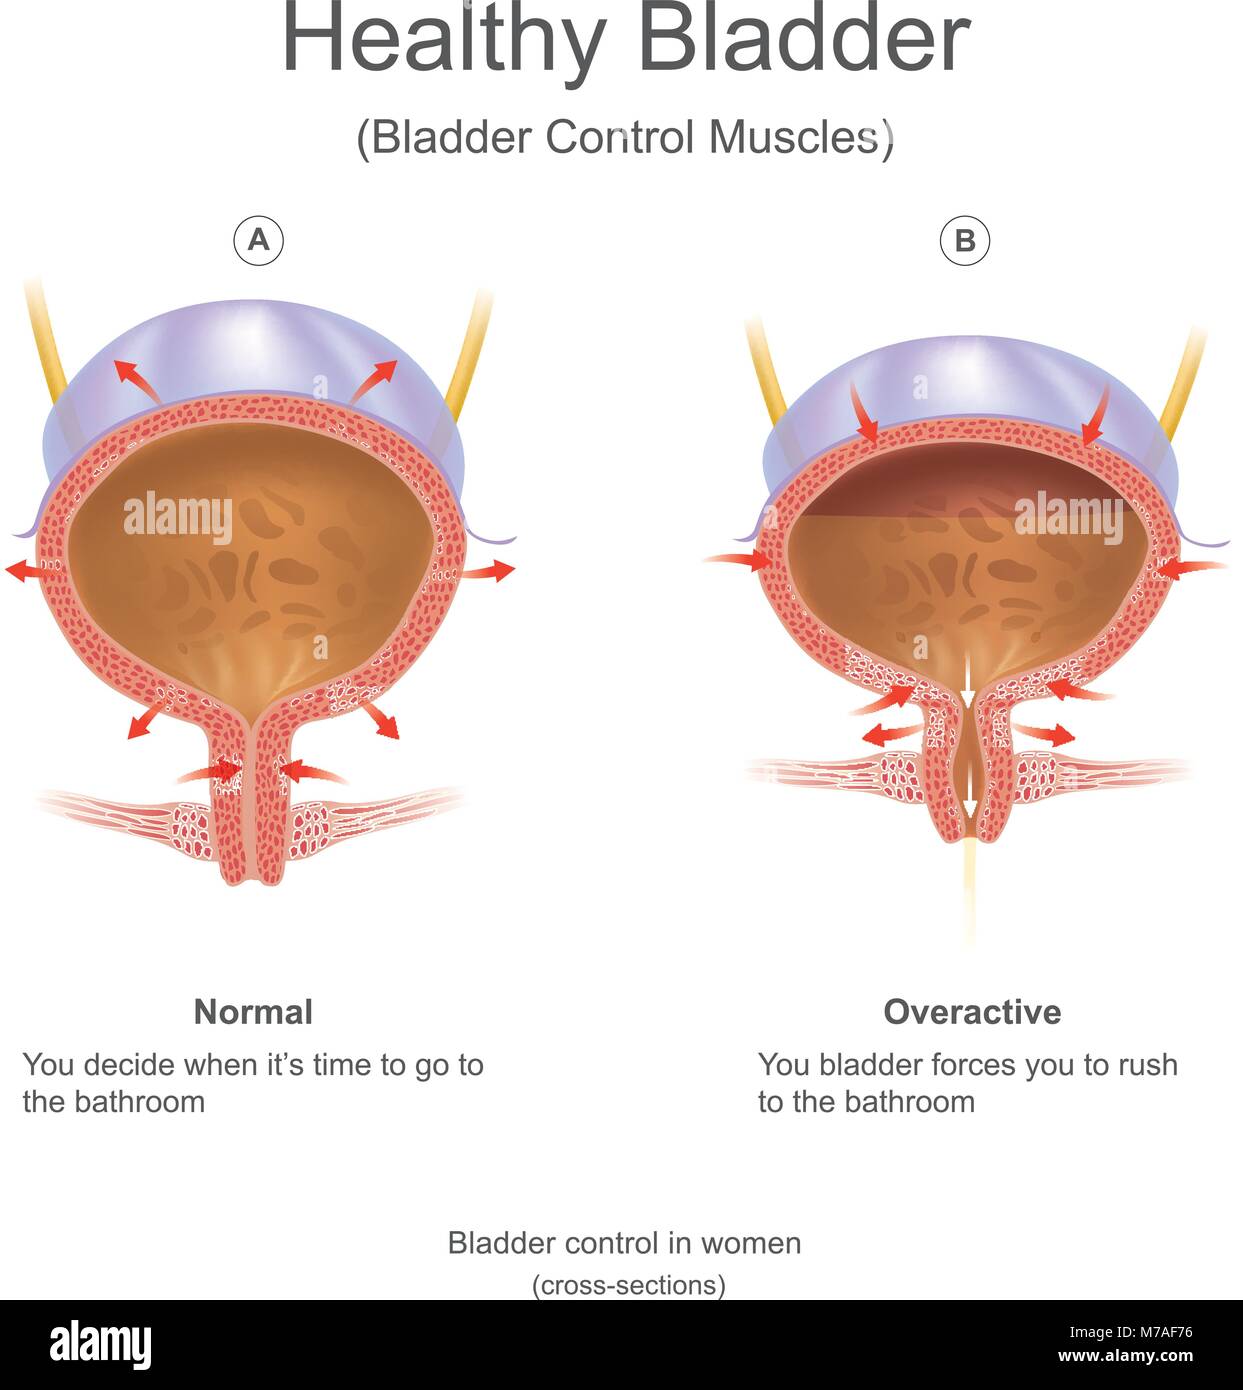

La vescica nell'uomo la vescica è una cava muscolare e distensible (o elastico) organo, che si siede sul pavimento pelvico. L'urina entra nella vescica Illustrazione Vettorialehttps://www.alamy.it/image-license-details/?v=1https://www.alamy.it/foto-immagine-la-vescica-nell-uomo-la-vescica-e-una-cava-muscolare-e-distensible-o-elastico-organo-che-si-siede-sul-pavimento-pelvico-l-urina-entra-nella-vescica-176637754.html

La vescica nell'uomo la vescica è una cava muscolare e distensible (o elastico) organo, che si siede sul pavimento pelvico. L'urina entra nella vescica Illustrazione Vettorialehttps://www.alamy.it/image-license-details/?v=1https://www.alamy.it/foto-immagine-la-vescica-nell-uomo-la-vescica-e-una-cava-muscolare-e-distensible-o-elastico-organo-che-si-siede-sul-pavimento-pelvico-l-urina-entra-nella-vescica-176637754.htmlRFM7AF76–La vescica nell'uomo la vescica è una cava muscolare e distensible (o elastico) organo, che si siede sul pavimento pelvico. L'urina entra nella vescica